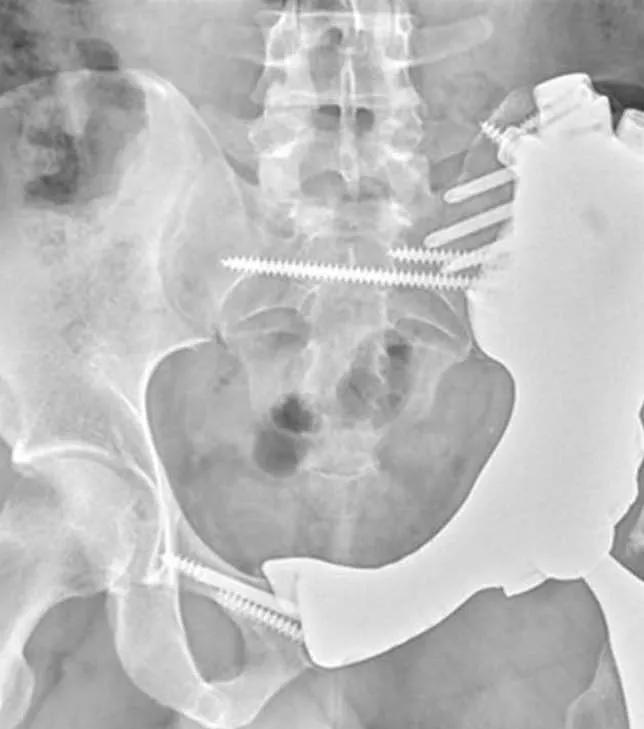

X-ray of pelvis implant

Left: Engineers created a 3D rendering of the hemipelvis, mapping screw trajectories (green lines) and suture holes meant to guide soft tissue attachments (light blue lines). The pelvis implant was anchored into the sacrum and the right hemipelvis, where bony ingrowth occurred after approximately three months. Right: One year after surgery.